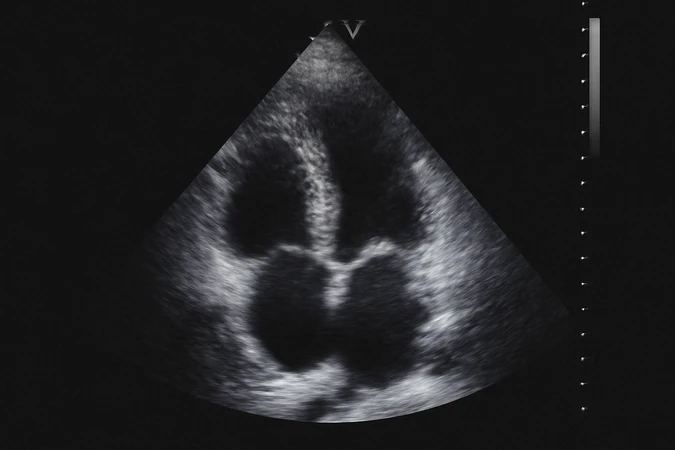

Pemeriksaan ekokardiografi (ultrasonografi jantung) pada anak-anak untuk mendeteksi kelainan jantung.

- Ekokardiografi adalah prosedur yang aman, tidak menimbulkan rasa sakit, dan tidak menggunakan radiasi, sehingga sangat disarankan untuk pasien dengan masalah jantung atau pembuluh darah

Ekokardiografi⠀adalah pemeriksaan jantung yang menggunakan gelombang suara (ultrasonik) untuk menghasilkan gambar dari jantung dan pembuluh darahnya. Metode ini adalah cara non-invasif yang sangat efektif untuk melihat struktur dan fungsi jantung tanpa perlu melakukan operasi atau prosedur yang lebih invasif.

Fungsi⠀Ekokardiografi

- Menilai fungsi jantung

- Memeriksa struktur jantung

- Mendeteksi penyakit jantung

- Mengevaluasi cairan di sekitar jantung

Bagaimana Ekokardiografi

- Pasien diminta untuk berbaring di meja pemeriksaan dan mengenakan pakaian yang memungkinkan akses ke dada

- Untuk TTE, gel khusus (gel ultrasonik) akan dioleskan ke dada untuk memudahkan penghantaran gelombang suara

- Probe diletakkan di dada untuk mengirimkan gelombang suara, dan gambar jantung akan ditampilkan di layar komputer